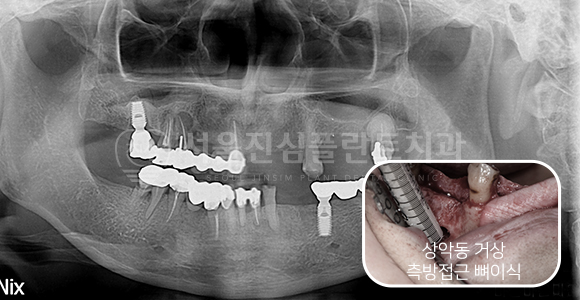

Ridge splitting + 뼈이식 임플란트

BEFORE

AFTER

하악 매우 좁은 골폭에 Ridge splitting + 뼈이식 상악동 거상술 + 뼈이식

상악동 거상 측방접근 + 고난이도 뼈이식 임플란트